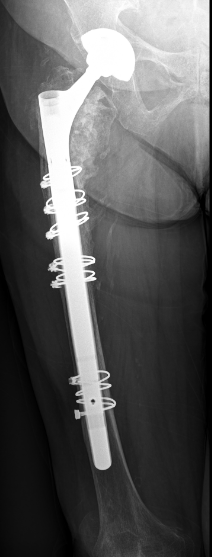

Minimal invasive Hüftgelenkersatz